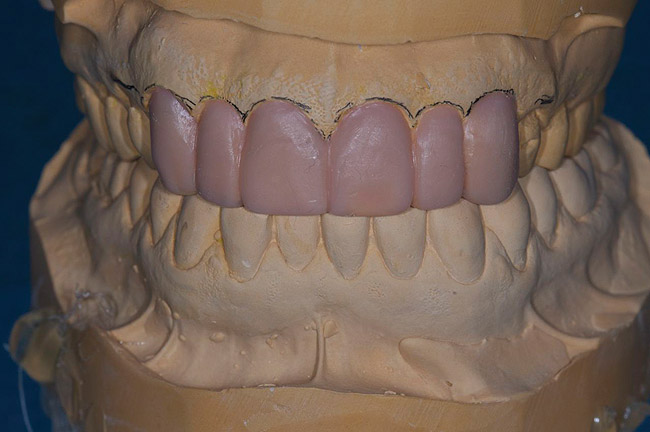

Figure 6  Incisal edge and lingual contour added to the maxillary anteriors.

Figure 6

Figure 7  Length added to the incisal edge of mandibular anteriors and contoured to the proper occlusal plane.

Figure 7

Figure 8  The articulator is closed and the tooth coupling evaluated. If the teeth touch and the incisal pin is on the table, the vertical relationship is ideal.

Figure 8